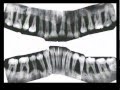

Пульпит является одним из наиболее распространенных заболеваний зубов, которое происходит из-за воспаления пульпы — мягкой ткани, находящейся внутри зуба. Для предотвращения пульпита следует соблюдать ряд важных мероприятий.

Необходимо регулярно посещать стоматолога для проведения профилактических осмотров и чистки зубов. Специалист поможет выявить ранние признаки пульпита и предпринять своевременные меры для его предотвращения или лечения.